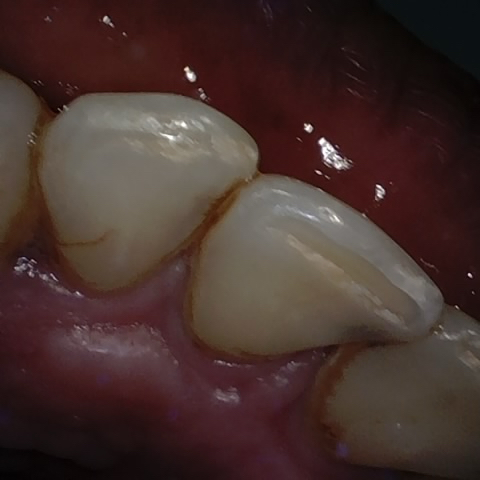

Annotated as "Good"